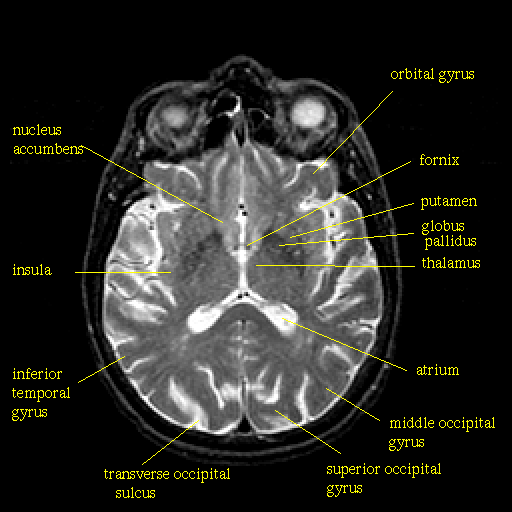

T2-weighted structural MR: Slice 28

Slice 28